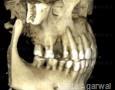

CBCT :

Yes

Pictures

Baseline